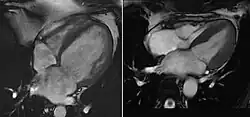

Bildgebung

Im Röntgen-Thorax ist der Herzschatten verbreitert. In der Echokardiographie und in der Kernspintomographie sieht man eine Erweiterung der Ventrikel und der Vorhöfe. Die Wand des linken Ventrikels ist meist verdünnt, der linke Ventrikel kugelig umgeformt und allseits vermindert beweglich (kontraktil).

Die Auswurffraktion ist reduziert. Der Abstand zwischen vorderem Mitralsegel und Septum ist vergrößert. Oft liegen eine Mitralklappeninsuffizienz und eine Trikuspidalklappeninsuffizienz vor.